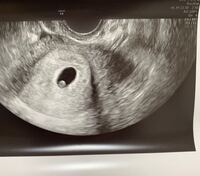

カブしょこのチャンネル登録お願いします:https//googl/W4US1z浜田翔子 → https//wwwyoutubecom/channel/UCfwqD2iS2nC0QAOQqlcW1Kw 運営中 6w3dに心拍確認できる確率と、心拍確認できている人の特徴がわかる 6w3d時点での胎芽の平均的な大きさがわかる 6w3dにエコー検査を受けた妊婦さん60名の、Instagramのアカウントとブログを調査し、統計を取りました。 60名全員の妊娠経過を追っていますので 心拍確認とは? お腹の赤ちゃんが無事に生きているか、卵管などの異所性の妊娠ではないか、医師が超音波(エコー)検査によって子宮内にある赤ちゃんの心臓の動きを確認することをいいます。 どうやって心拍確認するの? 心拍確認は超音波(エコー)検査で行います。 超音波検査には

心拍は 妊娠6週~妊娠7週ごろ 確認できることが多いようです。 私は医師から(胎嚢確認の)2週間後に再診するように言われました。 妊娠7週3日の診察で、ドクドクと とても早い赤ちゃんの脈の音 を聞くことができました。 また、前回はほとんど確認 前日の7w3dに出血があったことから、医師より「赤ちゃんも心拍も見えないときの出血は、すでに流産が始まっているということかもしれない」と話がありました。8w3dに再診し、18mmの空っぽの胎嚢を見て流産が確定しました。 7w6dに受診。心拍確認できず→流産 ⑦ この方は前回受診時より胎嚢 トピ主さんの赤ちゃん、元気に心拍確認出来ると言いですね! トピ内id: 閉じる× 閉じる× 思い出して涙が しおりをつける